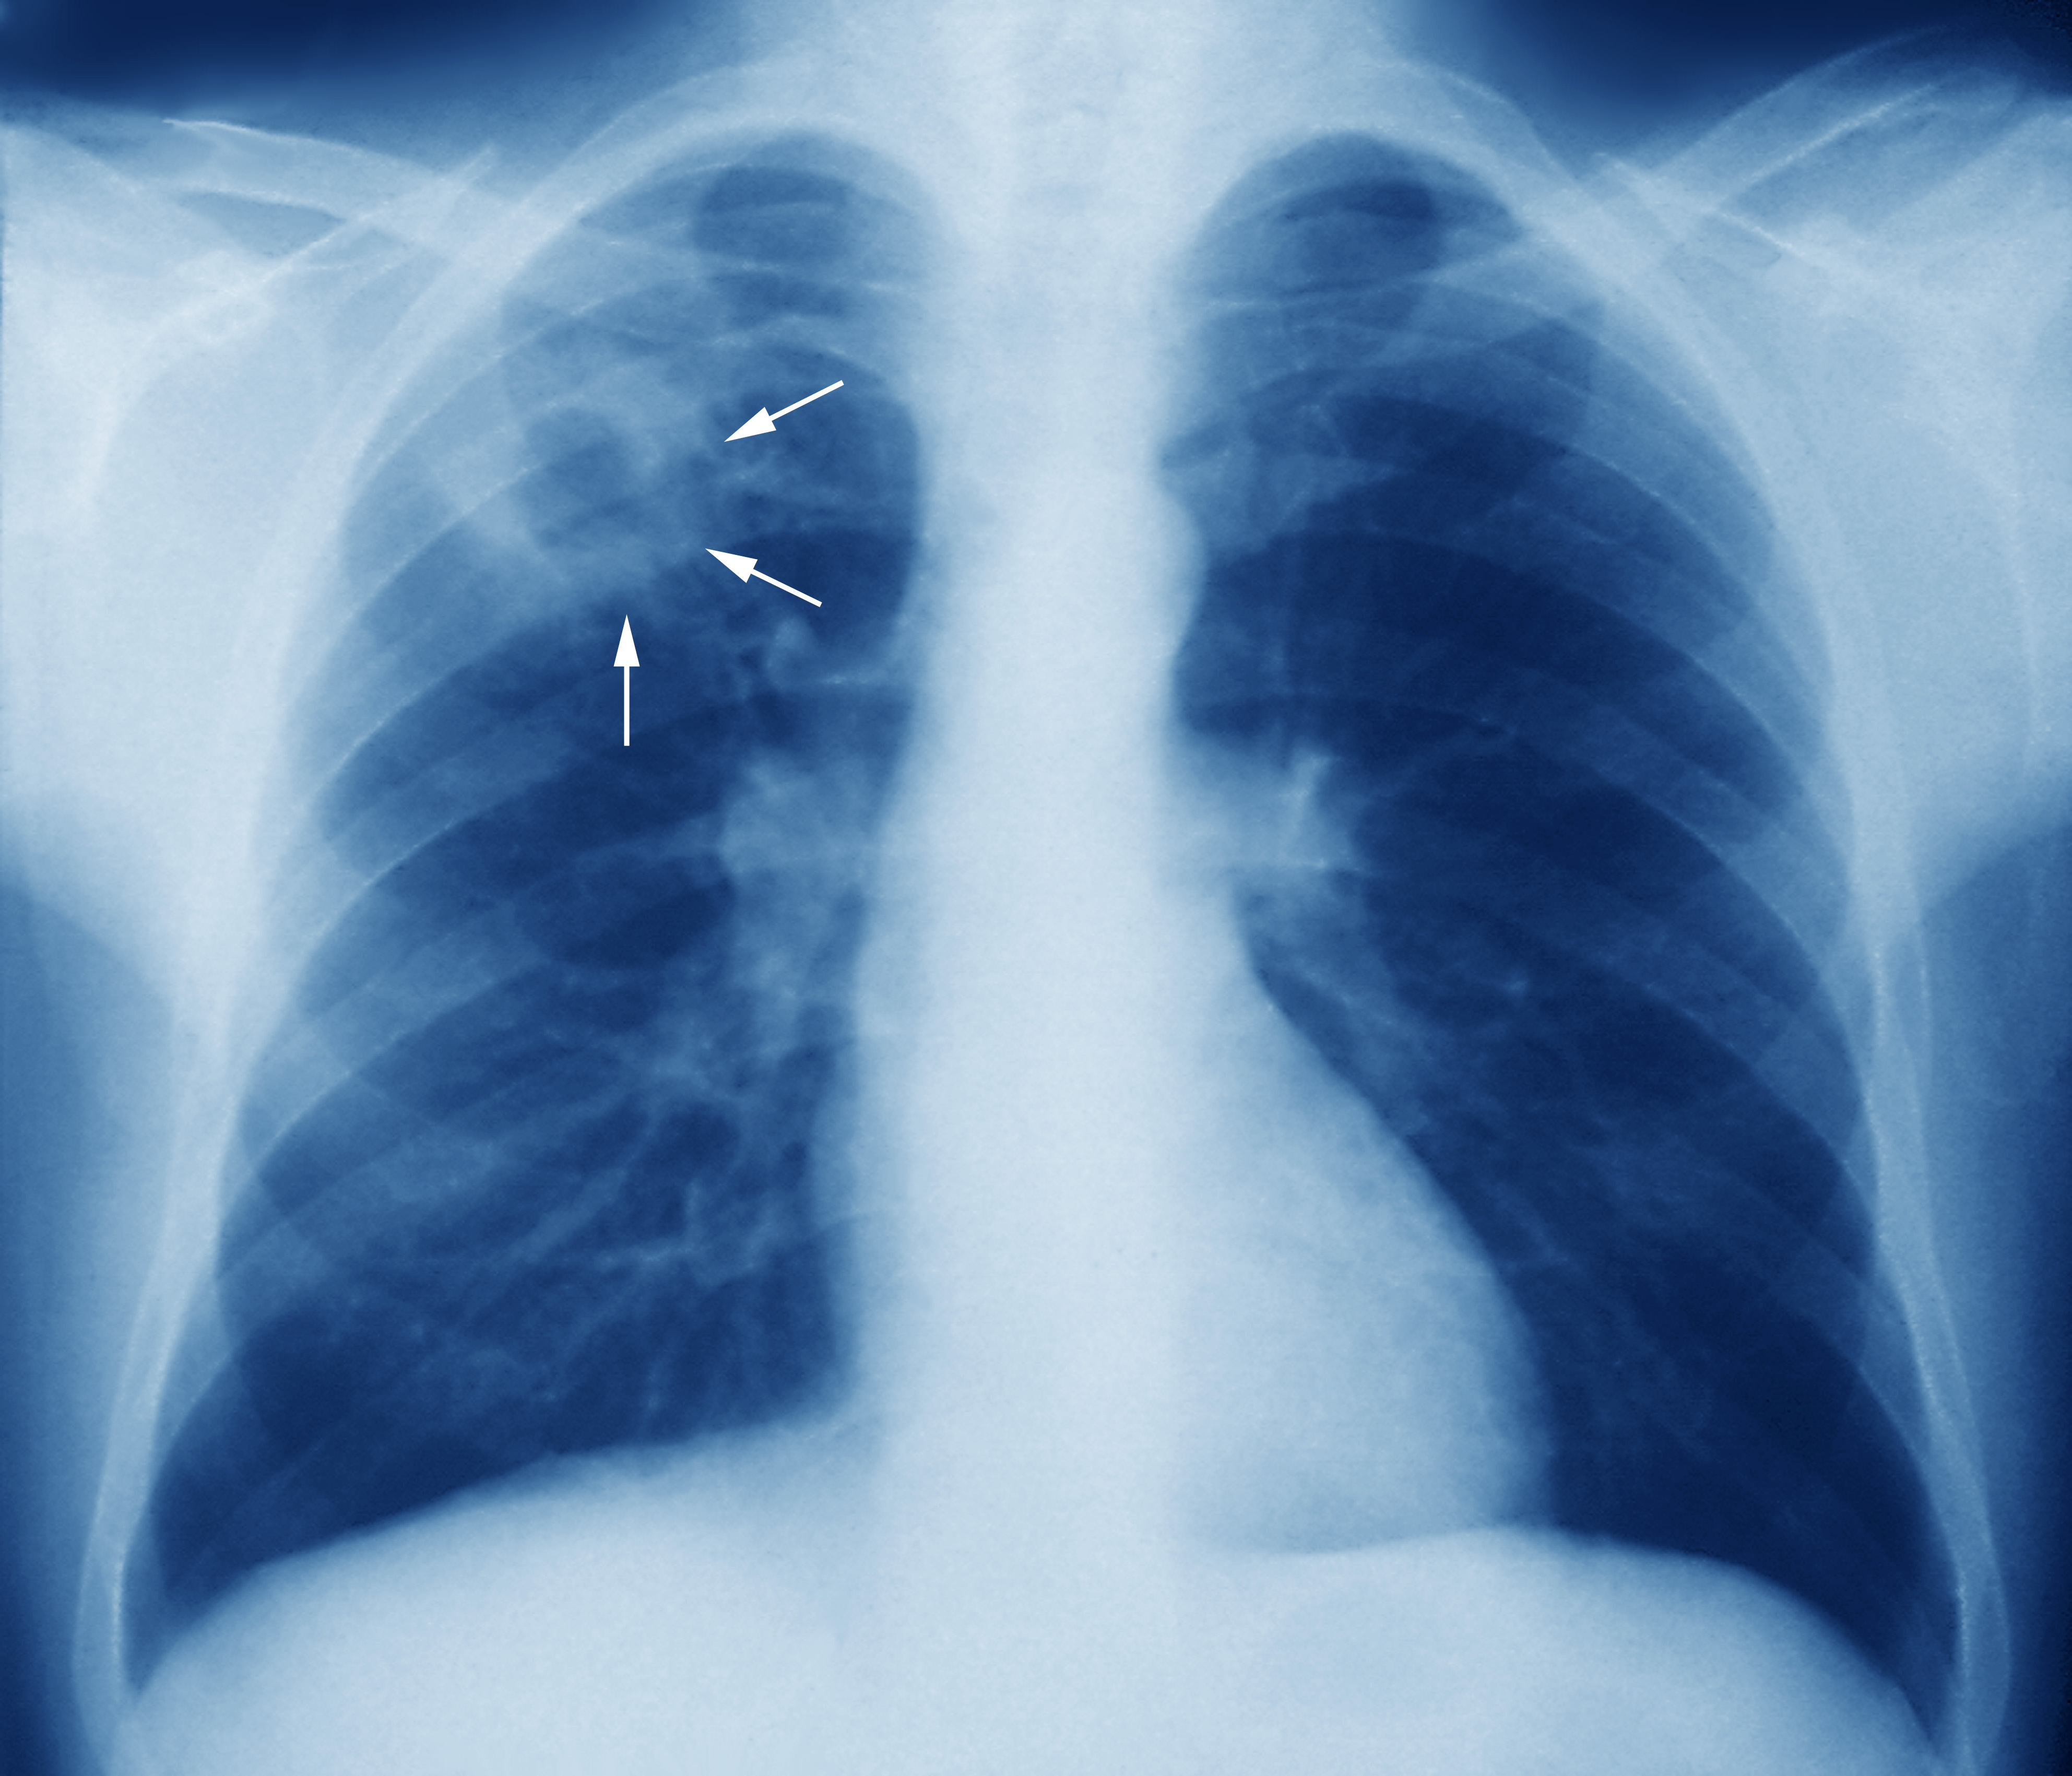

Honduras, entre los países de Latinoamérica con más casos de tuberculosis

TUBERCULOSIS